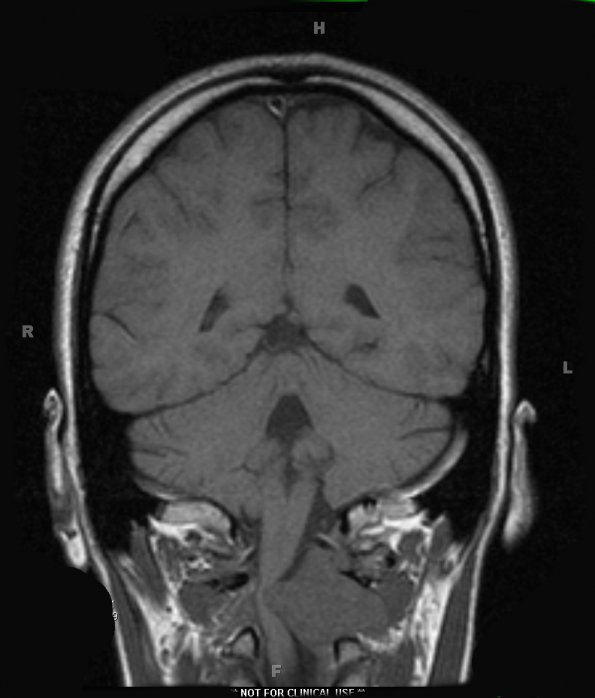

Case 17 History ---- The patient was a 22 year old woman with a 2 month history of numbness in her hands bilaterally. The numbness increased when lying down. She also has pain in her right shoulder. She saw a chiropractor who performed cervical manipulation that did not help the symptoms. She was involved in a motor vehicle accident several months prior to her current presentation with possible symptom exacerbation. Physical exam showed paresthesias as well as subtle motor difficulties in her hand. ---- 17A1,2 T1-weighted MRI without (17A1) and with contrast (17A2) shows a solid enhancing mass in the left paraspinal tissue with extension through the C1-C2 foramen into the extradural space with marked cord compression. The clinical differential diagnoses included schwannoma and meningioma. Operative procedure: Tumor resection.